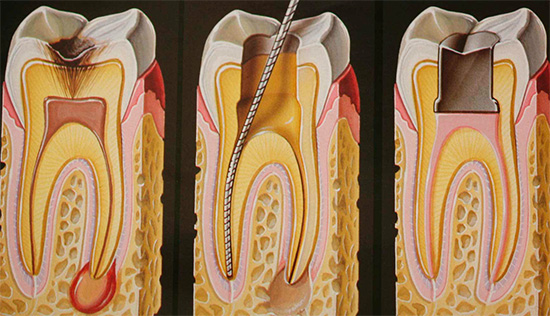

Etapas do tratamento de cárie profunda

O tratamento da cárie profunda consiste em uma série de etapas realizadas pelo dentista na ordem necessária para a situação clínica em questão.

- Anestesia Este é um estágio importante do alívio da dor na perda de dentes durante a fase de tratamento. Permite que o paciente se sinta confortável e não tenha medo.

- Tratamento mecânico de cavidades de tecidos cariados (preparação), irrigação medicamentosa com anti-sépticos.

- Almofada de tratamento à base de hidróxido de cálcio - às vezes usada no tratamento de cárie profunda e colocada na parte inferior da cavidade cariosa para evitar os riscos de pulpite (inflamação dos tecidos moles). Sua atividade antibacteriana é conhecida há muito tempo.

- Colocação de juntas isolantes. Ao preencher com uma amálgama ou compósito (exceto cimentos de ionômero de vidro), é necessário o isolamento do material da dentina, a fim de evitar o efeito tóxico dos componentes incluídos na composição de preenchimento. Para a colocação no tratamento de cárie profunda, aplique: cimentos de fosfato de zinco, cimentos de ionômero de vidro, compômeros (combine as propriedades de SIC e compósitos), etc.

- E, finalmente, a formulação do selo, selecionado de acordo com as características da cavidade a ser preenchida.